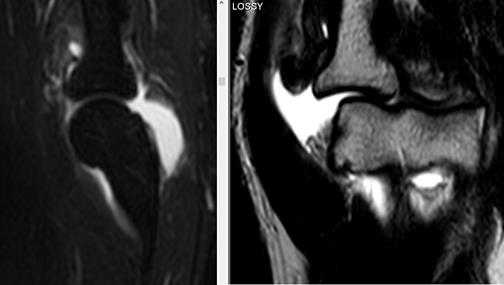

МР-признаки незначительного синовита локтевого сустава; отечность мягких тканей (трехглавой мышцы плеча и глубокого сгибателя пальцев) нижней поверхности сустава; нельзя исключить минимальные проявления посттравматического липоартрита.

МР-картина структурных изменений в виде фокуса и очага отека трабекулярной костной ткани локтевого отростка локтевой кости и головки лучевой кости. Нерезко выраженный синовит.

МР-картина частичного разрыва сухожилия двуглавой мышцы плеча. Признаки частичного повреждения дистальных отделов сухожилия плечевой мышцы, в большей степени в месте прикрепления. Начальные проявления артроза локтевого сустава. Синовит. Отек медиальных отделов периартикулярных мягких тканей.